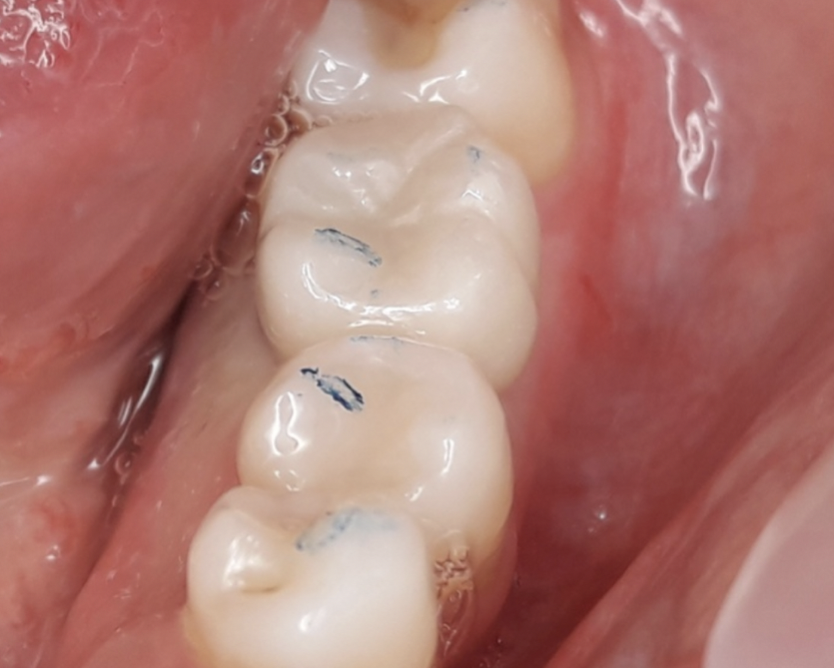

Nello studio sono stati inclusi 20 pazienti (12 donne e 8 uomini) di età compresa tra i 28 e i 65 anni, con edentulia singola e conseguente deficit vestibolare dei tessuti molli. La matrice dermica a elevata consistenza è stata opportunamente ritagliata mediante forbici e lama ed è stata posizionata al di sotto del lembo muco periostale allestito con approccio a spessore totale, vestibolarmente alla cresta ossea in cui è stato posizionato contestualmente un impianto endosseo osteointegrabile. Non si è utilizzato alcun ausilio di fissazione per la matrice dermica che è stata stabilizzata dal solo lembo di accesso ribaltato su di essa e suturato, mediante punti staccati semplici, al lembo linguale.

Le rilevazioni eseguite a distanza di 18 mesi di tempo medio, hanno mostrato un netto miglioramento del PES (Pink Esthetic Score) con un punteggio medio superiore a 9 (eccellente) e in due casi un punteggio tra 6 e 8 (buono). La sovrapposizione dei file .stl provenienti dalla scansione della arcata dentaria interessata prima dell’intervento e a distanza di 18 mesi ha permesso di rilevare un incremento medio in senso orizzontale di 2 mm in media.